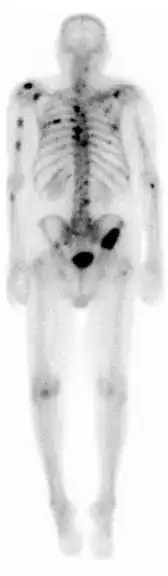

![]() A nuclear medicine whole-body bone scan. The nuclear medicine whole-body bone scan is generally used in evaluations of various bone-related pathology, such as for bone pain, stress fracture, nonmalignant bone lesions, bone infections, or the spread of cancer to the bone. | |

A bone scan or bone scintigraphy /sɪnˈtɪɡrəfi/ is a nuclear medicine imaging technique used to help diagnose and assess different bone diseases. These include cancer of the bone or metastasis, location of bone inflammation and fractures (that may not be visible in traditional X-ray images), and bone infection (osteomyelitis).[1]